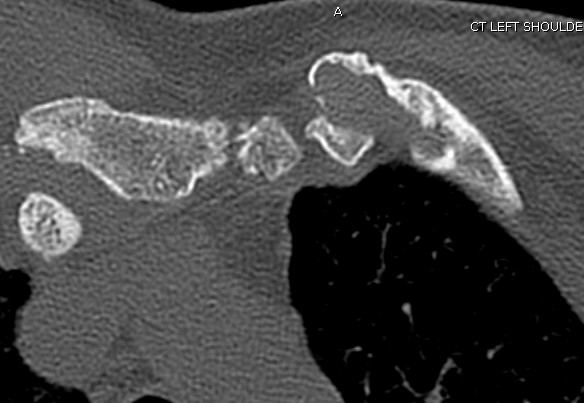

CT scan

Left posterior SCJ dislocation with pre- and post angiogram

Left posterior SCJ dislocation with pre- and post angiogram

Severe left posterior SCJ dislocation with subclavian vein compression

Adolescent

Can be medial clavicle physeal injury up to age 25

Management

Cardiothoracic surgeon available in case vascular injury occurs